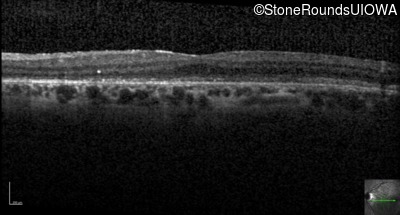

Optical Coherence Tomography - Left - 20/200

Exemplar / OCT Stack